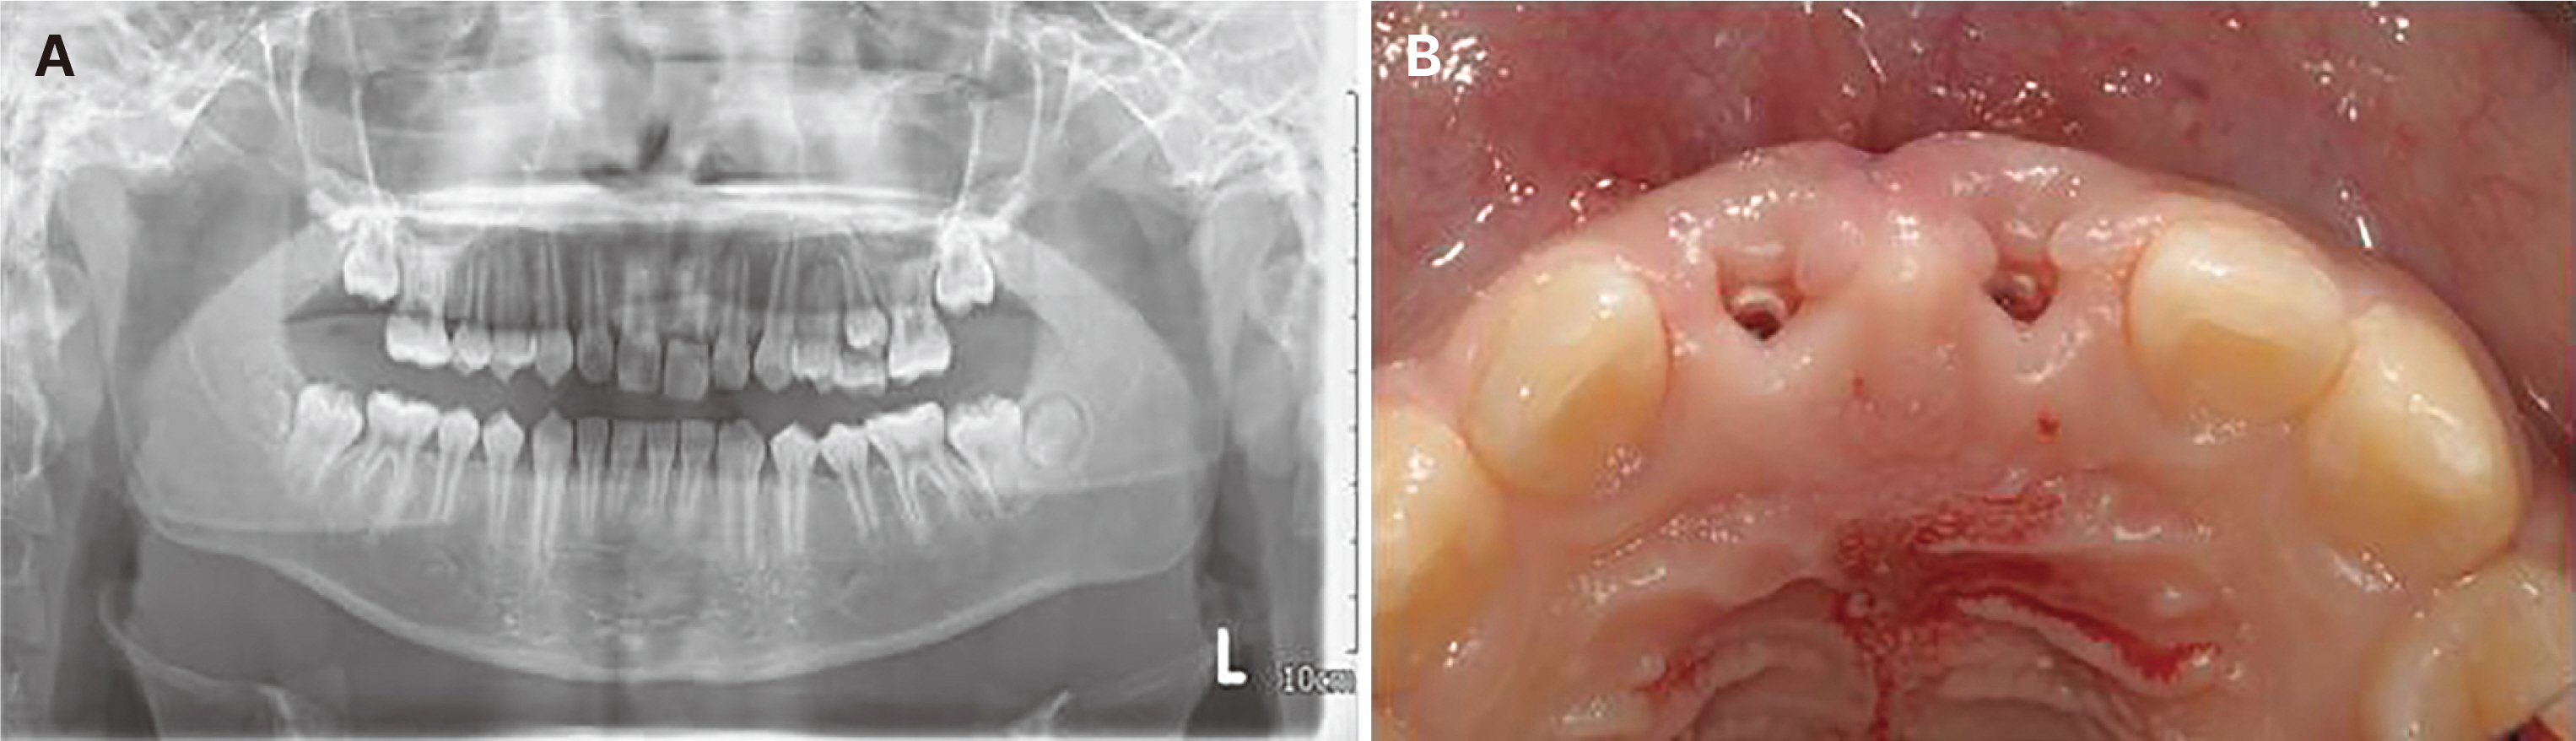

- Immediate implant placement and immediate loading in the anterior maxilla is an effective approach to rapidly address aesthetic demands. To achieve successful outcomes, bone quality, soft tissue condition, and accurate implant positioning are essential factors. For optimal results, procedures such as bone augmentation, precise implant placement, and, when necessary, soft tissue grafting should be considered. Furthermore, provisional restoration play a crucial role in achieving the desired appearance of prosthetic restorations and improving the aesthetics of the soft tissue. By performing soft tissue molding through provisional restoration, an ideal emergence profile can be established, which can be subsequently transferred to the final prosthesis, leading to a functional and aesthetically pleasing restoration. This approach aims to optimize the aesthetic outcomes in the anterior region while preserving the natural contours of the peri-implant soft tissue. In this case, a patient requiring extraction of maxillary anterior tooth underwent immediate implantation and alveolar bone grafting using a guide fabricated in advance from CT data. The patient received a provisional restoration on the same day. Subsequent steps included transitioning from the provisional prosthesis to the definitive prosthesis, ultimately achieving an aesthetically pleasing and functional implant restoration. We report this case to highlight the successful approach to maxillary anterior implant rehabilitation.